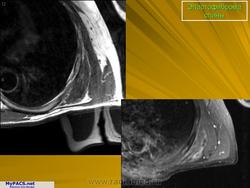

Эластофиброма.

Эластофиброма — редкая, нечетко отграниченная опухоль, локализующаяся преимущественно в мягких тканях спины, особенно в лопаточной области, у пожилых лиц, чаще женщин. Изредка имеет семейный, но чаще посттравматический характер. Макроскопически представляет собой плотноватый или мягкий, серовато-белый узел диаметром 10—15 см, который имеет резиновую консистенцию и редко бывает двусторонним. Опухоль способна прорастать периост подлежащих костей (лопатка, ребра). В анамнезе у больных нередко отмечается травма той зоны, где впоследствии возникла эластофиброма. Под микроскопом отмечается почти полное отсутствие фибробластов и фиброцитов в очаге, который представлен коллагенизированными и гиалинизированными структурами, а также грубыми оксифильными, нередко ШИК-положительными эластическими волокнами.

Макроскопически эластофиброма представляет собой округлое или сферическое образование диаметром в среднем 5-10 см. На разрезе ткань серо-белого цвета, нередко с фокусами кистознои дегенерации и включениями жировой субстанции, подобная фибролипоме. Микроскопически основу образования составляет примерно одинаковое количество отечных эозинофилвных коллагеновых и эластических волокон, связаннвк с редко встречающимися фибробластами. Обнаруживаются также небольшие участки интер-стициального мукоидного материала и различного размера скопления жировых клеток. Типична дегенерация эластических волокон, фрагментация их в небольшие глобули или капли, имеющие линейное расположение в виде бус. Поврежденные волокна в ультрафиолетовом свете дают зеленую флюоресценцию. Наиболее вероятно, что эластофиброма является псевдоопухолью дегенеративного характера. Подтверждением концепции реактивного процесса являются медленная прогрессия образования, иногда возникающее двустороннее поражение, а также преобладание у лиц. род деятельности которых связан с тяжелыми физическими нагрузками, Однако, поскольку подобное поражение возникает у небольшого числа таких людей, можно предположить наличие генетической предрасположенности или наследственного энзимного дефекта. В литературе есть данные о наличии эластофибромы у 3 родственников. Существует несколько предположений, объясняющих механизм ее образования. Согласно одному из них, эластофиброма возникает в связи с чрезмерным образования коллагена с последующим формированием эластоподоб-ного материала в результате травматизации коллагеновых волокон. Согласно другому это образование развивается вследствие гиперпродукции патологически измененных эластичных волокон, вторично подвергающихся повреждению при травматизацией тканей, например между углом лопатки и грудной стенкой.

Эластофиброма